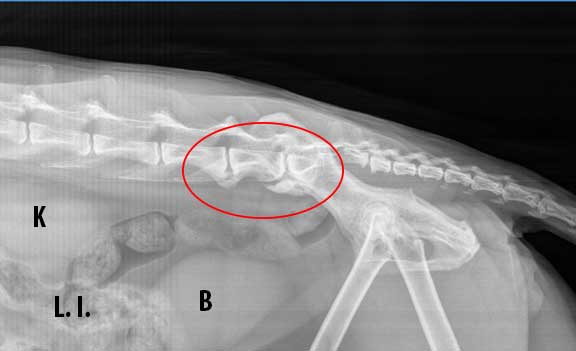

- X-rays: Imaging helps visualize joint health and any abnormalities.